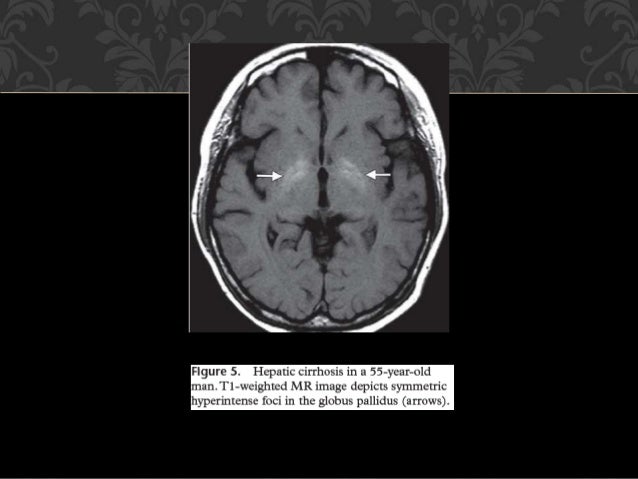

Lesiones Bilaterales De Los Ganglios De La Base Y El Talamo

es.slideshare.net